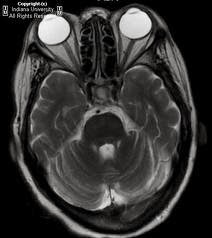

Tolosa-Hunt

syndrome

In

addition to the whole ophthalmic exam as labelled above, the doctor must carefully

look for facial hypoesthesia or bulge oforbital venous congestion, ocular

superficial vessels.